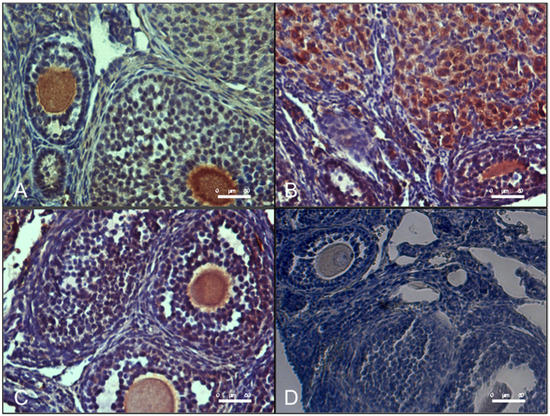

As shown in Figure 6, ovaries from DHEA mice presented an increased level of MG-AGE as evaluated by immunohistochemical analysis. Administration of carnitine formulation 2 but not 1 was able to prevent MG-AGE accumulation, with levels similar to controls.

Figure 6.

Oral administration of carnitine formulation 2 prevents the accumulation of methylglyoxal-advanced glycation end-products (MG-AGE) induced DHEA. Part of paraffin embedded sections of formalin-fixed ovarian tissue were processed immunohistochemical analysis of MG-AGE accumulation. Representative images of immunolocalization of MG-AGE in CTRL (A), DHEA (B), DHEA + C1 (C) and DHEA + C2 (D) ovaries are shown.